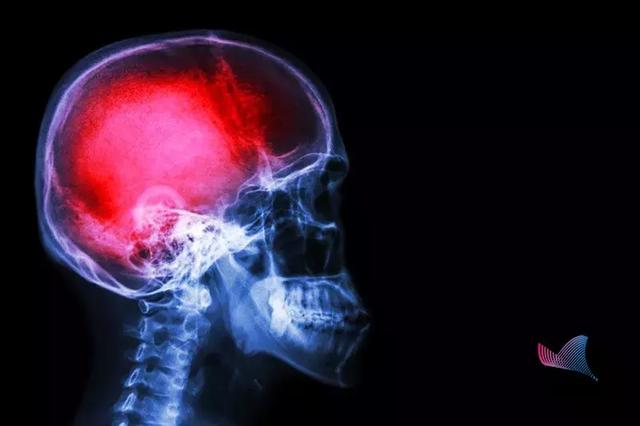

中風

第一殺手,是造成中國人壽命損失的第一大病因。據WHO數據顯示,我國腦卒中的發生率位居世界第一。

我國每年腦卒中發生病例500余萬,其中約有196萬人死亡。

也就是說,

腦卒中

每6.2秒就有一人發生,每16秒就有一人死亡!腦卒中已成為我國居民死亡首要因素。更可怕的是,中風不僅僅是老年人的專利,在我國

腦卒中,又稱中風,很多人對中風的認識只是停留在患者會口眼歪斜、口齒不清。

什么是腦卒中?

當附著在血管壁的栓子脫落,堵塞腦部血管時,形成缺血性中風。而當腦血管破裂,顱內出血時,就會形成出血性中風。